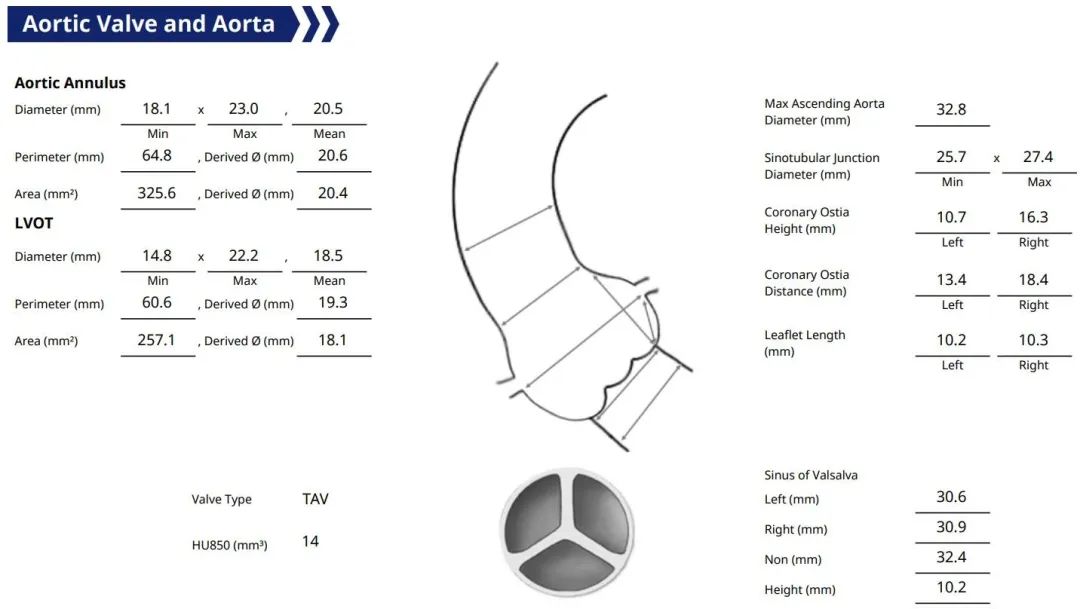

术前CT评估

三叶式主动脉瓣,瓣叶显著增厚伴轻度钙化,LVOT偏直筒;水平夹角约48°

• 三叶式主动脉瓣,瓣叶显著增厚,L-R交界局部增厚粘连,轻度钙化,钙化结节位于右窦瓣缘;收缩期LVOT偏直筒;

• 左冠开口高度<12mm,右冠脉开口高度可,切线位测量,无冗长瓣叶;

• 瓦氏窦、STJ内径可,升主动脉无扩张,瓣上40mm处约32mm;

• 左心室内径稍偏小,心肌肥厚;

• 主动脉瓣水平夹角约48°,非横位心,主动脉弓宽度角度可;